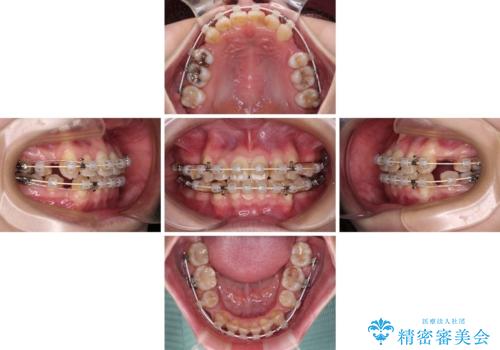

- 矯正装置

- 審美装置

- 治療期間

- 2年6ヶ月